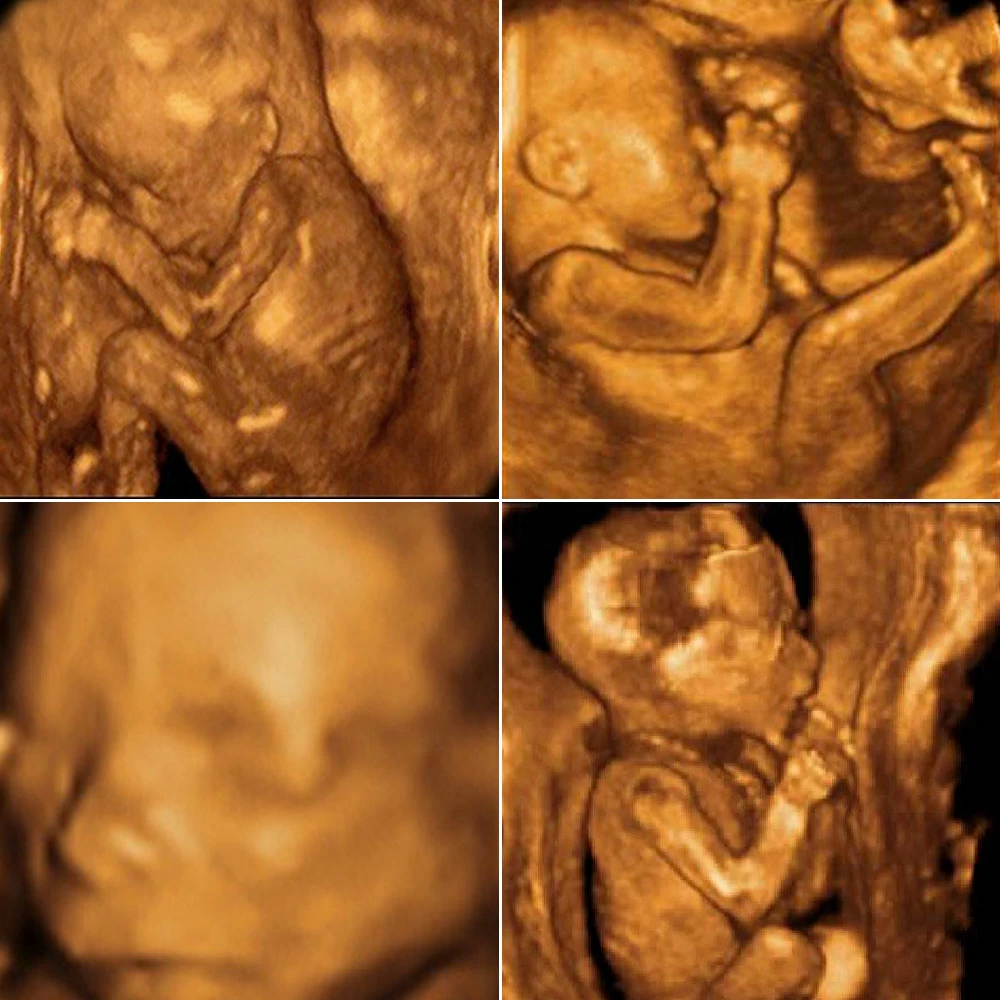

Головной мозг имеет маленькие размеры, но точно повторяет все структуры мозга взрослого человека, плод может сжимать и разжимать пальцы в кулак, захватывает большой палец и активно его сосет.

К концу недели у плода появляются брови и ресницы, хорошо заметна шея.

Копчиково-теменной размер к концу недели составляет 70-75 мм Начинают появляться зародыши молочных зубов под верхней и нижней челюстями. Лицо полностью сформировано, нос и глаза (полностью сомкнуты веками).